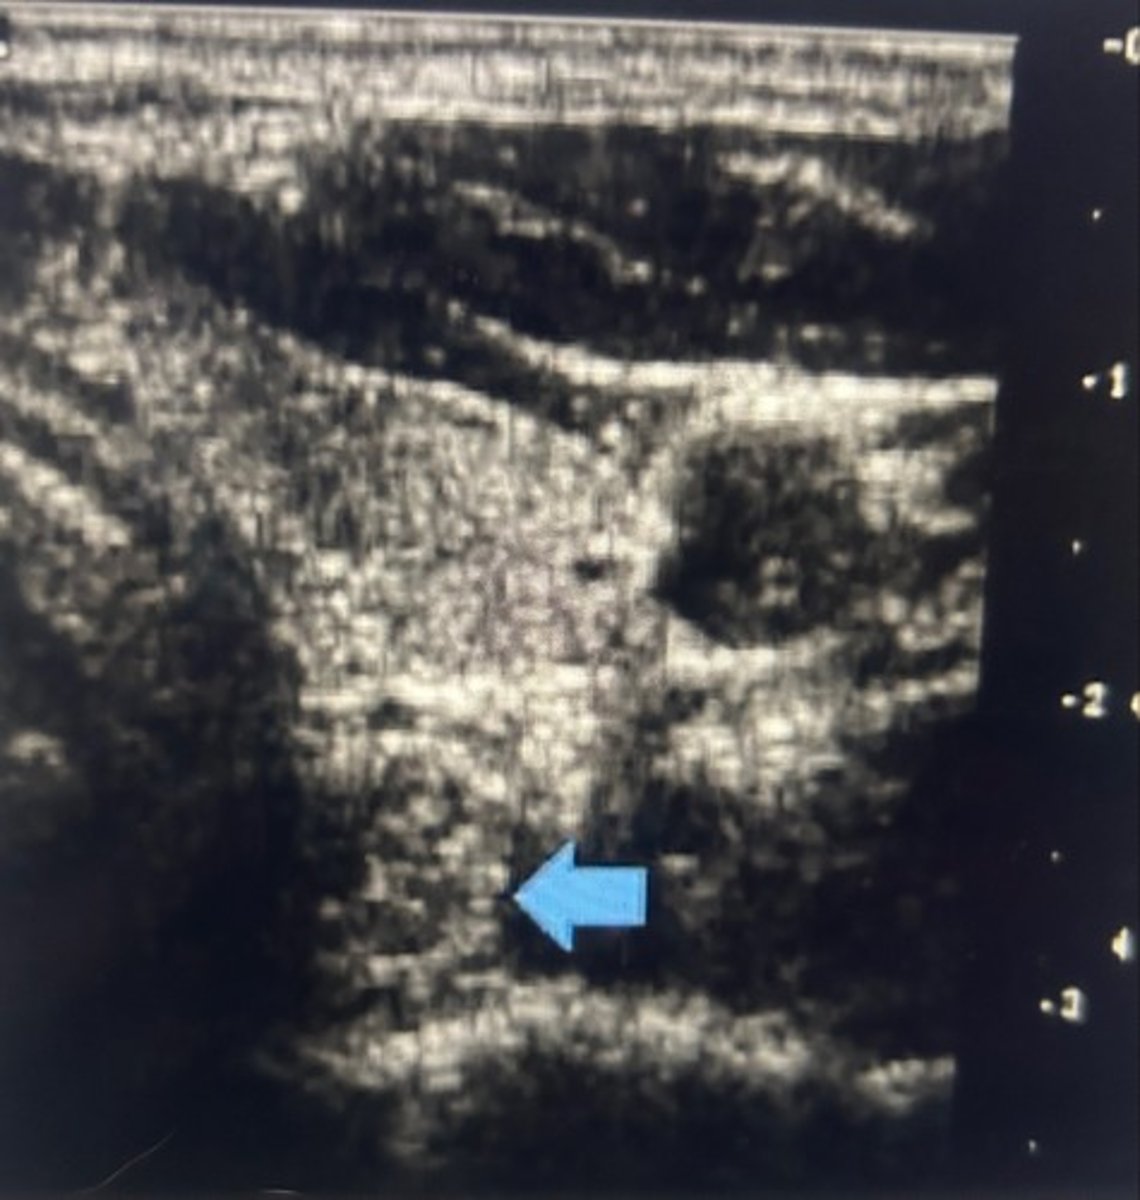

While performing a thyroid, ultrasound, you notice the area indicated by the blue arrow, which of the following statements is true regarding completing this patient exam

Request that the patient swallow to better evaluate the area